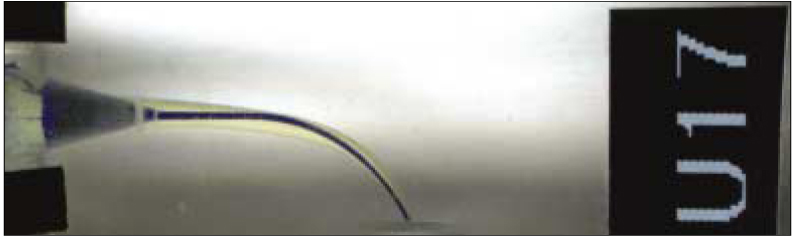

Figure 1

Sample of superimposed image (ProTaper Universal).

Purple; Pre-instrumented canal, Yellow; Post-instrumented canal

3. Post-instrumented image taking and superimposition

After the root canal preparation was completed, the enlarged canal was filled with Vitapex (Neo Dental Chemical Products co., LTD, Tokyo, Japan) to enhance the contrast of the post-instrumentation image. Then the resin block was scanned again at the reproducible position. The pre- and post-instrumented canal images were superimposed on one another with the guide of attached label using Adobe Photoshop ver.7.0 (Adobe, San Jose, California, USA) (Figure 1). These superimposed images of 2736 × 944 pixel size were inspected on the TFT-LCD monitor (SyncMaster CX1565N; Samsung, Suwon, Korea) at 1024 × 768 screen resolutions.